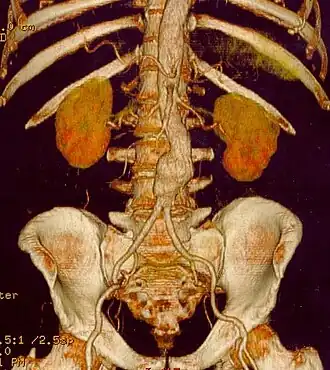

Aneurisma de aorta abdominal

O aneurisma da aorta abdominal corresponde à dilatação da porção abdominal da artéria aorta. Ocorre mais frequentemente em homens, tabagista e hipertensos.[2]

O diagnóstico do aneurisma da aorta abdominal é feito com ultra-sonografia do abdome, tomografia computadorizada ou ressonância magnética.